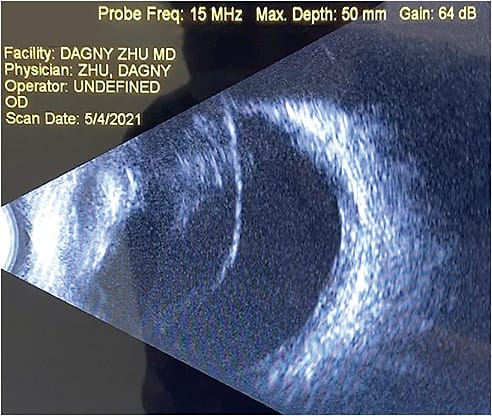

Before any intervention, surgeons should confirm the diagnosis by evaluating the patient’s subjective complaints, as well as objective exam findings. Floaters can be difficult to quantify objectively, as the patient may present with 20/20 visual acuity but complain of generalized blurred vision. The key is to ascertain whether patients see a “film” or “fog” moving across their vision. Often, they will describe their vision as fluctuating in nature, and their vision may “clear up” as the opacity moves out of their central vision with their eyes’ changing gaze. Some patients will also describe seeing “cobwebs”, “strings”, or “strands” within their vision. On slit-lamp examination, VOs can be visualized in the anterior vitreous space as dense syneresis, veils, or strands, similar to the patients’ subjective descriptions. They can also be visualized and grossly quantified on optical coherence tomography, ultrasound, and fundus photography. Contrast sensitivity testing can be used to more objectively assess its visual impact and as a tool to quantify improvement following treatment.